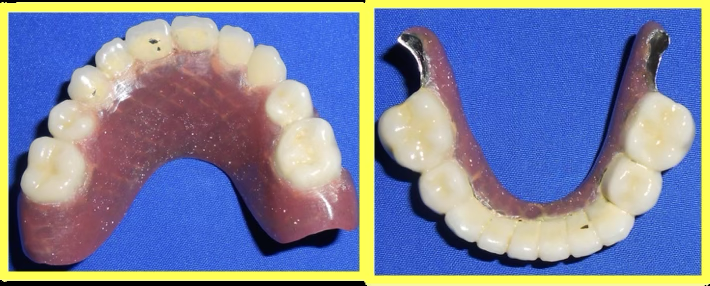

Custom telescopic copings were designed and fabricated to fit over prepared teeth, providing retention and support for the removable prosthesis.

Upper and lower telescopic removable metallic PFM prosthesis was carefully fitted, adjusted, and delivered to restore complete dental function and aesthetics.